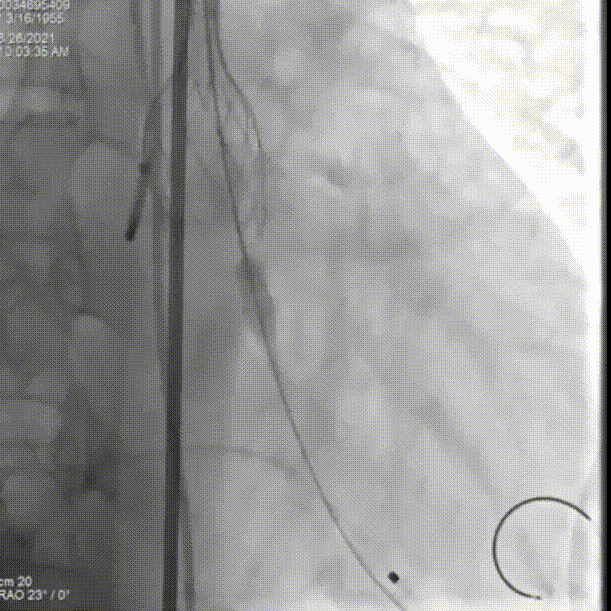

第一次尝试释放

位置偏深回收调整,进行第二次释放

瓣膜流入端被压缩有上跳风险,再一次进行回收

第三次释放